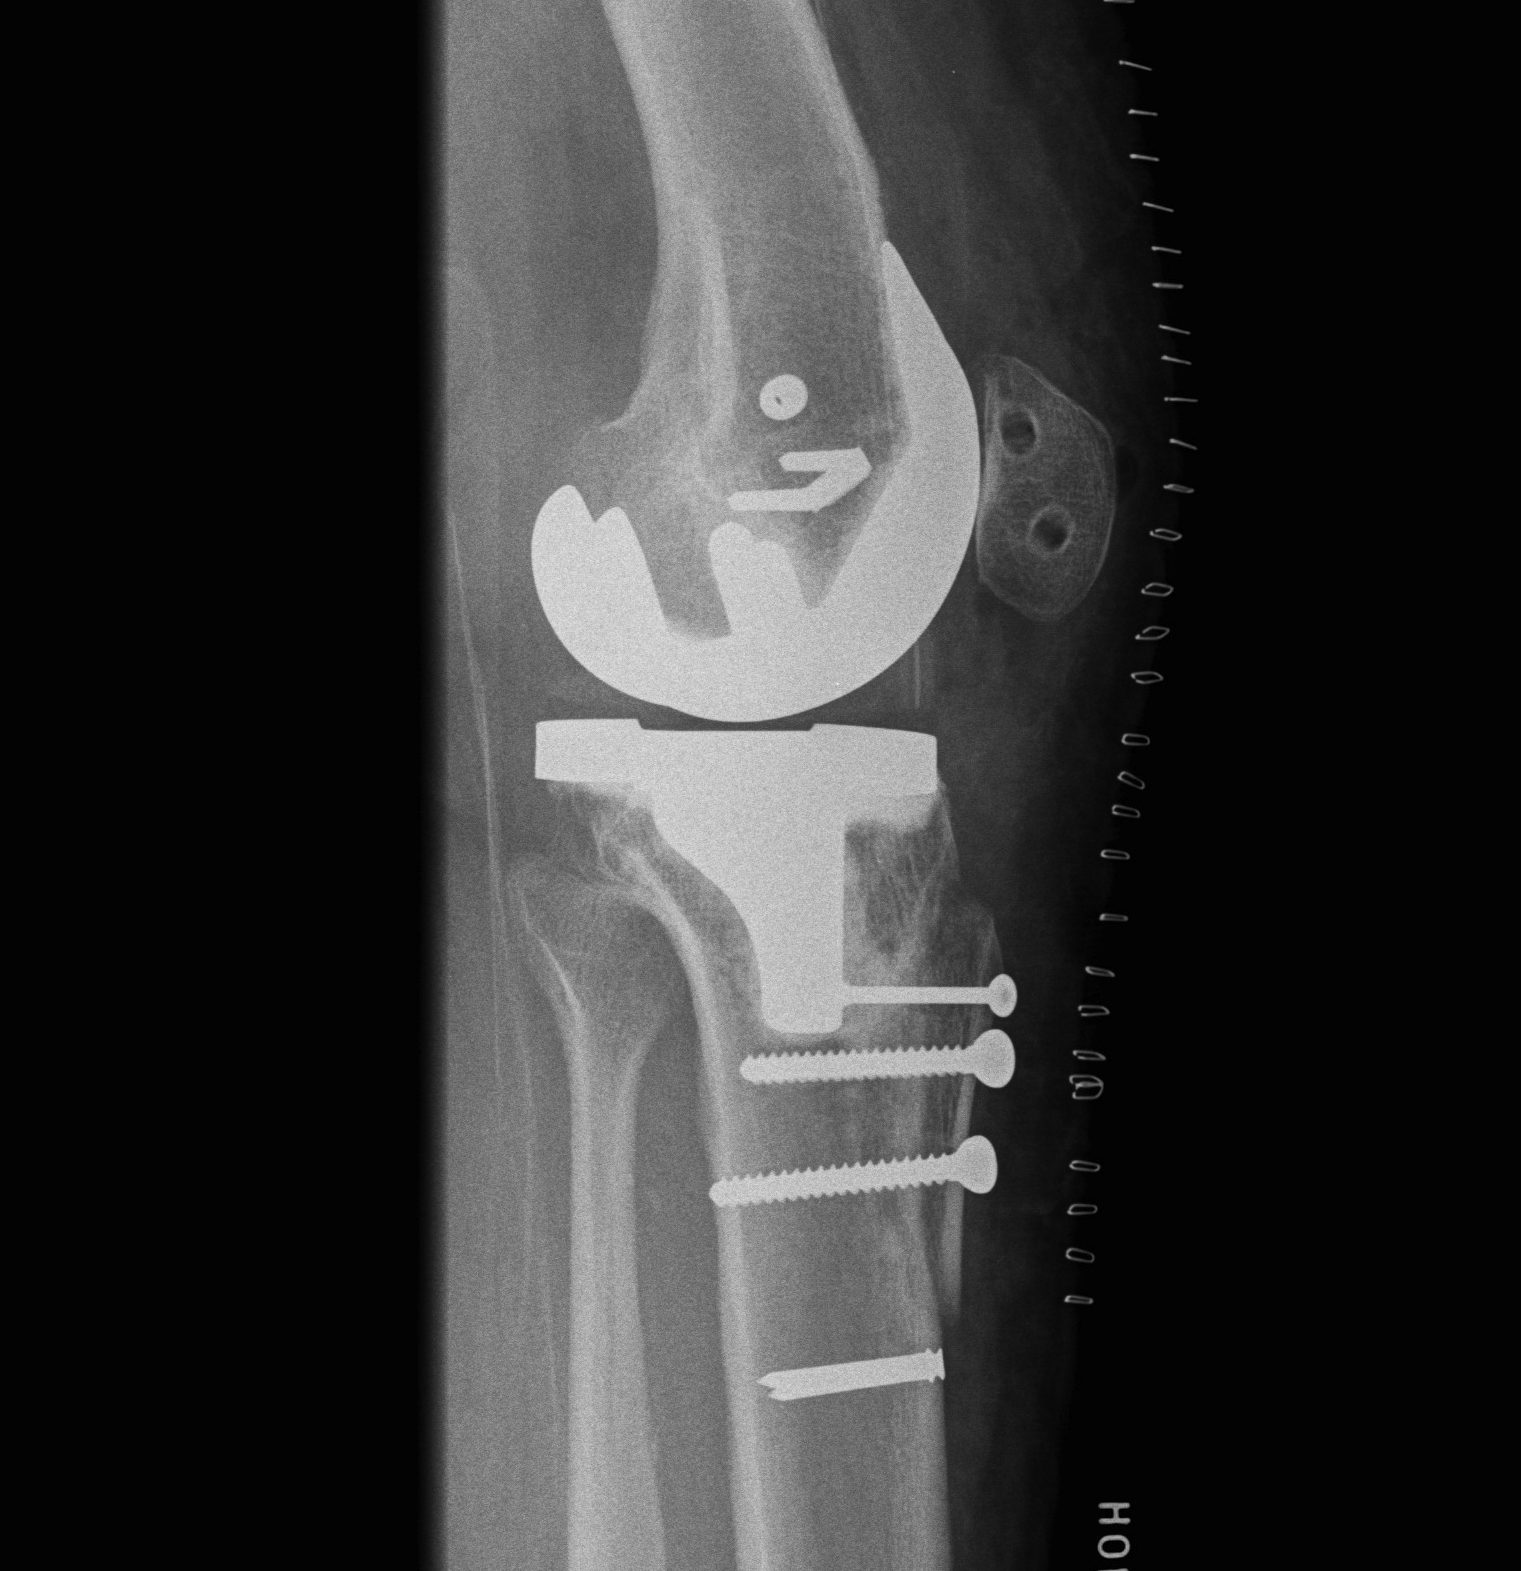

Xray

- skyline views

- lateral tilt / subluxation